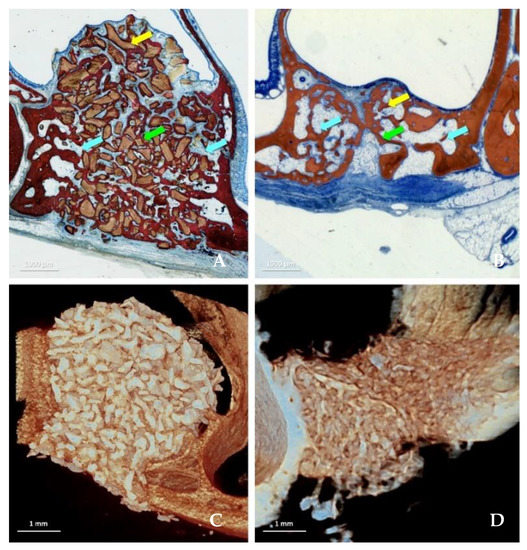

3. Results